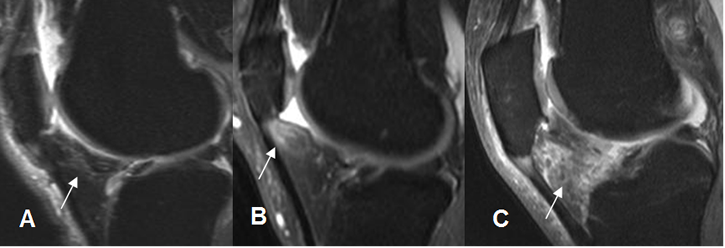

Fig 154. Hoffitis.

A, B y C: RM sagital en STIR. Zonas hiperintensas en la grasa infrapatelar, de grado variable y progresivo, por cambios inflamatorios.